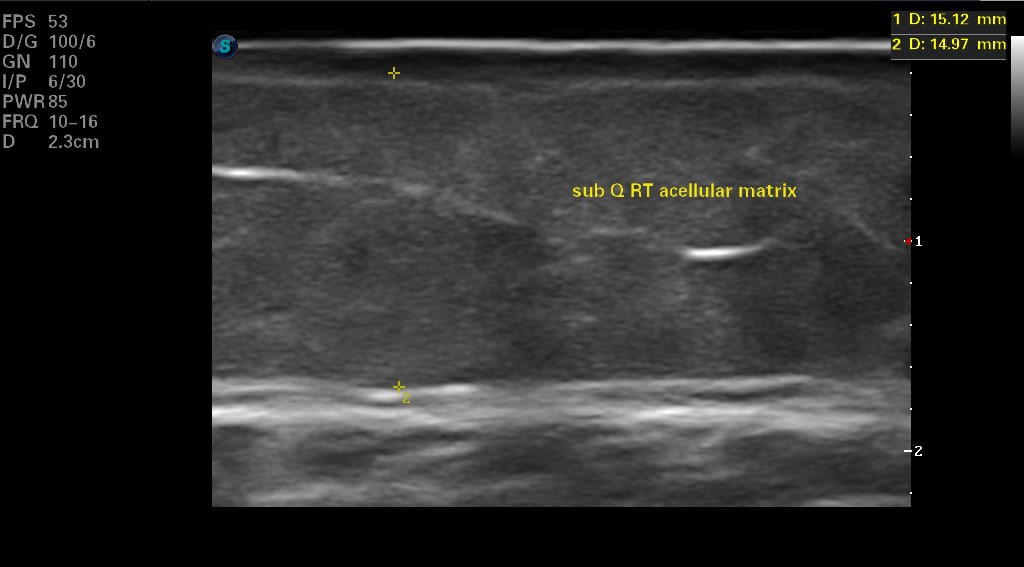

Sixteen months after initiating DECM therapy, the team performed ultrasound evaluation of the subcutaneous tissue for appearance and thickness of the fat, and the difference between the CTP and DECM healing was profound. On the right limb, the wound healed with a CTP occurred over the anterior compartment of the leg (just lateral to the tibial crest) and had remained healed for more than 5 years. The measurement of the subcutaneous tissue was 3.96–4.34mm thick (Figure 3). The physical appearance of that site was concave, atrophied, and with telangiectasia (Figure 4). The same limb healed with a DECM over the posterior compartment (just medial to the tibial crest) measured subcutaneous thickness of 14.97–15.12mm (Figure 5). The physical appearance was not concave, and the skin did not demonstrate telangiectasia, atrophy, or discoloration (Figure 6).